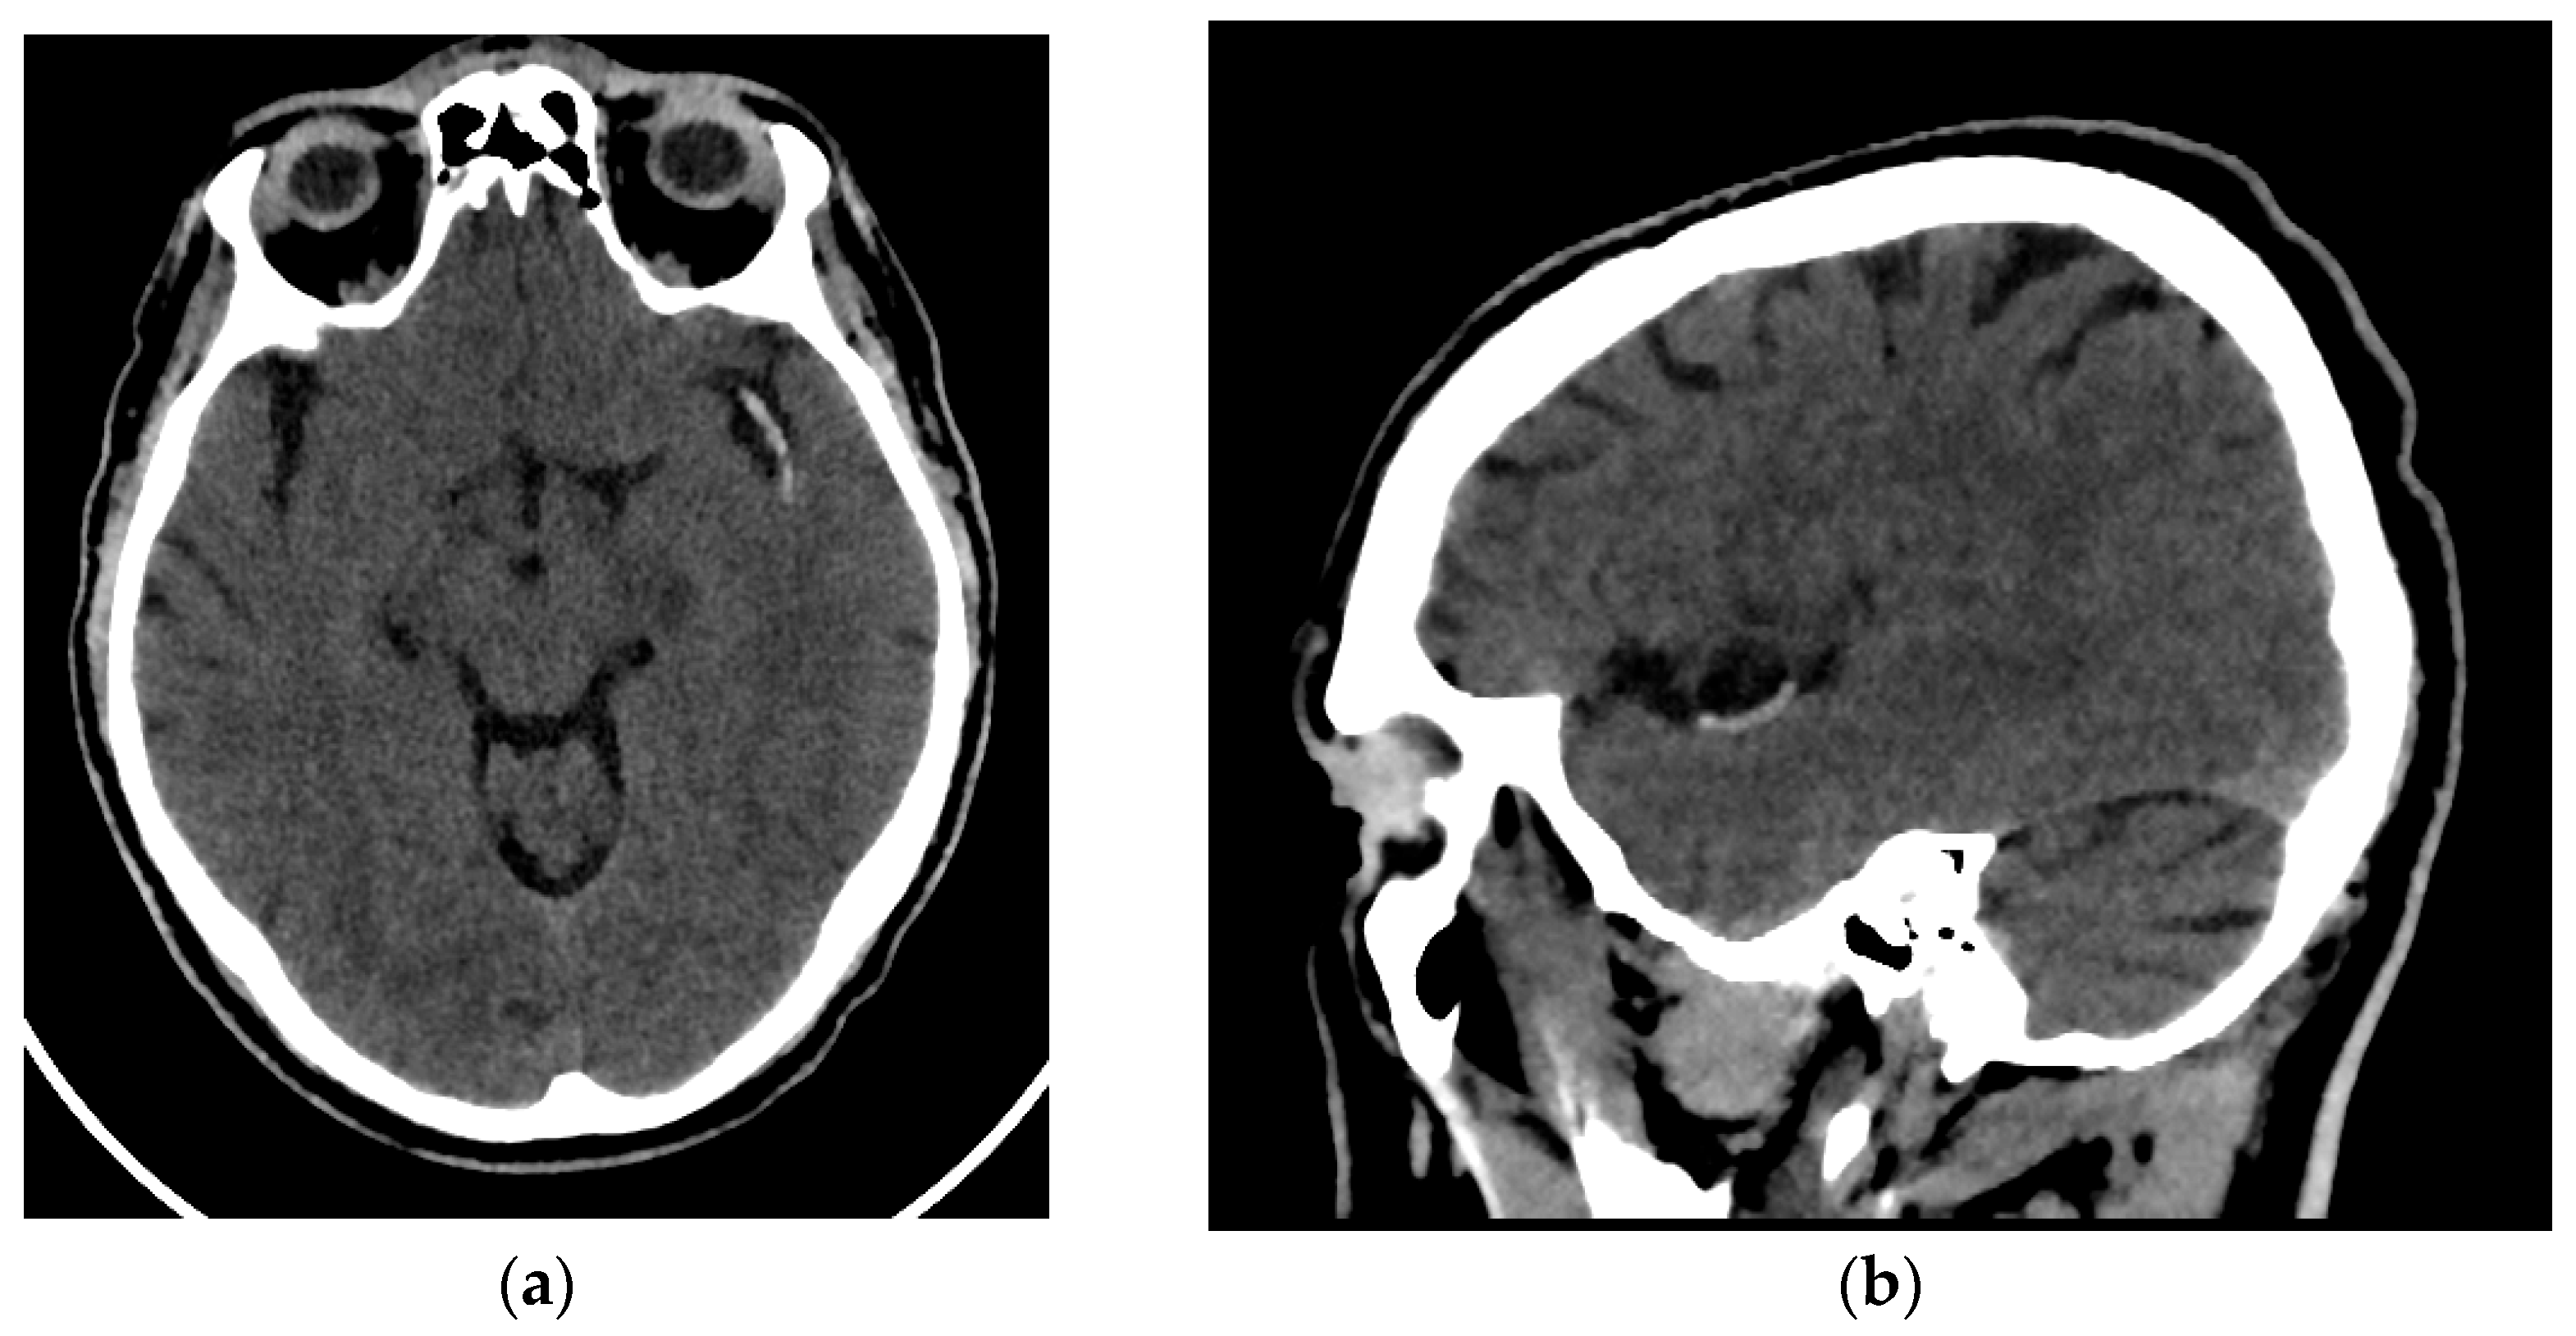

All patients enrolled in the study underwent an NCCT at our hospital utilizing one of two different CT scanners (16 rows of detectors, 120 kV) of the same make and model (Phillips Ingenuity; Amsterdam, The Netherlands) during the diagnosis process of AIS. Patients were randomly assigned to each scanner. The images obtained had a slice thickness of 0.625 mm. Although reconstructions with a thickness of 1 mm were available, they were not used for analysis. The window width and center were set at 80 and 40 Hounsfield units, respectively (Figure 1).

Figure 1.

Brain NCCT of a patient with AIS and the hyperdense MCA sign. This is one of the radiological signs of AIS in NCCT. (a) Axial NCCT scan of a patient with a hyperdense left MCA sign. (b) Sagittal NCCT scan of the same patient.